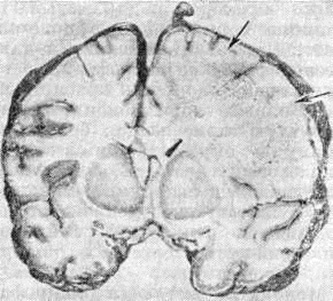

Рис. 1.

Фронтальный срез головного мозга больного, умершего от геморрагического лейкоэнцефалита: белое вещество справа более отёчное, усеяно мелкими петехиальными кровоизлияниями (указаны стрелками), прилежащие участки коры нечётко очерчены.

Патологическая анатомия. Макроскопическое исследование мозга при Лейкоэнцефалит выявляет расширение борозд и атрофию извилин. На срезе полушарий определяются различного размера участки деструкции и демиелинизации во всех отделах мозга, преимущественно в белом веществе, но захватывающие различные участки серого вещества коры (рисунок 1). В наиболее поражённых отделах мозг имеет губчатую консистенцию, желудочки мозга умеренно расширены.

Острый геморрагический лейкоэнцефалит. По клинические, и патоморфологический признакам эта форма Лейкоэнцефалит сходна с вирусными и поствакцинальными энцефалитами. При патологоанатомическом исследовании выявляют отёк мозга, на срезах в веществе мозга — большие очаги мягкой розовато-серой или желтоватой окраски с множественными точечными кровоизлияниями. Гисто л. картина характеризуется фибринозным некрозом стенок мелких сосудов, в основном венул, окружённых экссудатом фибрина, воспалительными клетками и кольцевидными геморрагическими зонами. В этих же периваскулярных зонах — демиелинизация с умеренной или выраженной деструкцией аксонов. На самых ранних стадиях периваскулярные инфильтраты представлены главным образом нейтрофилами, однако в более старых очагах находят много лимфоцитов и плазмоцитов.